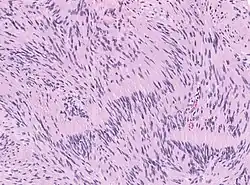

Die Therapie besteht in der chirurgischen Entfernung (Resektion) oder Bestrahlung. Anschließend erfolgt eine histopathologische Untersuchung des Operationspräparates unter dem Lichtmikroskop (Histologie).

- Histologisches Bild eines Schwannoms mit ausführlicher Erklärung